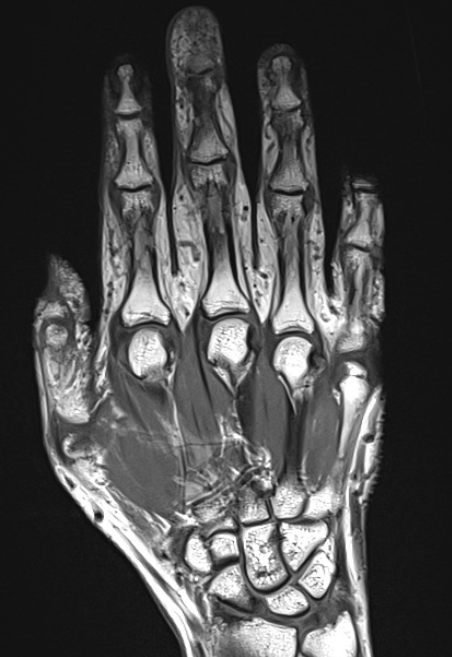

МРТ кисти

Магнитно-резонансная томография кисти – важный метод исследования, который позволяет оценить состояние кисти.